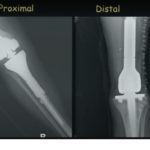

Proximal Fifth Metatarsal Fractures

There are three types of fractures at the proximal fifth metatarsal 1-Avulsion fracture 2-Jones fracture 3-Stress fracture Zone I injury = avulsion fracture •Relative incidence =93% •An avulsion fracture at the base of the fifth metatarsal . due to sudden hindfoot inversion resulting in tension along the lateral band of plantar aponeurosis which inserts into […]